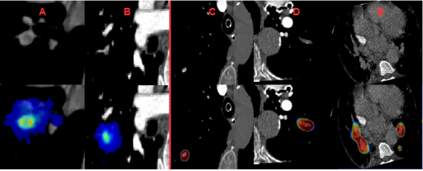

Pulmonary Embolisms (PE) represent a leading cause of cardiovascular death. While medical imaging, through computed tomographic pulmonary angiography (CTPA), represents the gold standard for PE diagnosis, it is still susceptible to misdiagnosis or significant diagnosis delays, which may be fatal for critical cases. Despite the recently demonstrated power of deep learning to bring a significant boost in performance in a wide range of medical imaging tasks, there are still very few published researches on automatic pulmonary embolism detection. Herein we introduce a deep learning based approach, which efficiently combines computer vision and deep neural networks for pulmonary embolism detection in CTPA. Our method features novel improvements along three orthogonal axes: 1) automatic detection of anatomical structures; 2) anatomical aware pretraining, and 3) a dual-hop deep neural net for PE detection. We obtain state-of-the-art results on the publicly available multicenter large-scale RSNA dataset.